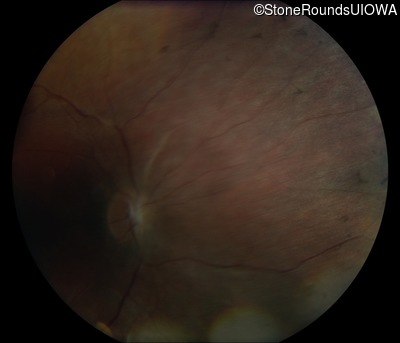

Fundus Photography - Right - No Light Perception

Exemplar